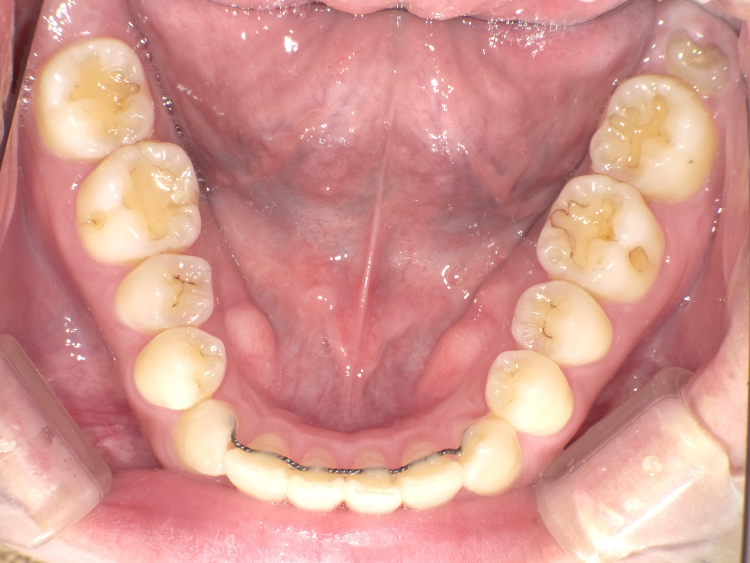

症例3

治療前

治療後

| 主訴 | 上下前歯全体の歯並びが気になる |

|---|---|

| 治療 期間 |

約6ヶ月 |

| 治療費 | 330,000円(税込)/調整費用別途 |

| 治療 内容 |

上下の前歯部にワイヤーを着けて進めていく、プチ矯正で施術。 |

| 治療の リスク |

固定の装置をつけないと後戻りしてしまう。 |